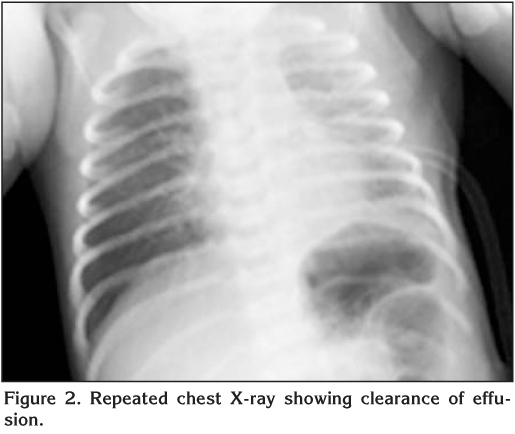

A 72 hour-old boy was admitted to our unit because of respiratory distress and feeding difficulty. The mother had no previous history of premature rupture of membranes. However, fever, pelvic pain, and abnormal vaginal discharge developed two days after delivery and she was given antibiotic treatment with suspect of puerperal sepsis. On admission, the patient was lethargic, cyanotic and tachypneic. Body temperature was 37?C, breath rate 66 per minute, and hearth rate 166 per minute. Intercostal and subcostal retractions were noted. Breath sounds could not be heard on the left lung. Chest X-ray showed shift of the mediastinum to the right, atelectasis and pleural effusion on the left side (Figure 1). Laboratory investigation revealed a hemoglobin of 15.5 g/dL, a hematocrit of 52%, a leukocyte count of 12.900/mm3. Serum C-reactive protein (CRP) level was high (286 mg/L, N: < 10 mg/L). Arterial blood gases revealed the following means: pH 7.18, PaO2: 53 mmHg, PaCO2: 50 mmHg, HCO3: 18.5 mmol/L, with an SaO2 of 78%. In thoracic ultrasonography, air bronchogram, consolidation, pleural thickening, and hyperechoic pleural collection (35 mm) compatible with empyema were observed on the left lung. Ampicillin and cefotaxime were given for empiric treatment. Supplemental oxygen was needed by oxygen hood to keep SaO2 > 90%. After draining the 30 cc of purulent fluid by thoracentesis, a chest tube was inserted and a closed chest drainage system was attached to promote drainage of fluid. Pleural effusion was purulent in character; pH 6.6, undetectable levels of glucose, protein 4.2 g/dL, and LDH: 15.600 IU/L. The analysis of cerebrospinal fluid sample was not compatible with meningitis. GAS was isolated from blood and pleural fluid cultures. Mother's urine and vaginal cultures, which were taken after the third day of antimicrobial treatment, were negative. However, subsequent increase in the antistreptolysin O titer, suggested streptococcus infection.

Figure 1

Chest X-ray and ultrasound are helpful both in the diagnosis of pleural effusion and for monitoring the course of parapneumonic effusion. Pleural fluid culture is an important diagnostic tool leading to identification of the bacterial pathogen in 60-80% of cases, in contrast to blood culture, which is positive in 13-31% (5). In our patient, chest X-ray and ultrasound showed the existence or clearance of pleural effusion and guided us in chest drain management. GAS was isolated from blood and pleural fluid culture of the patient.